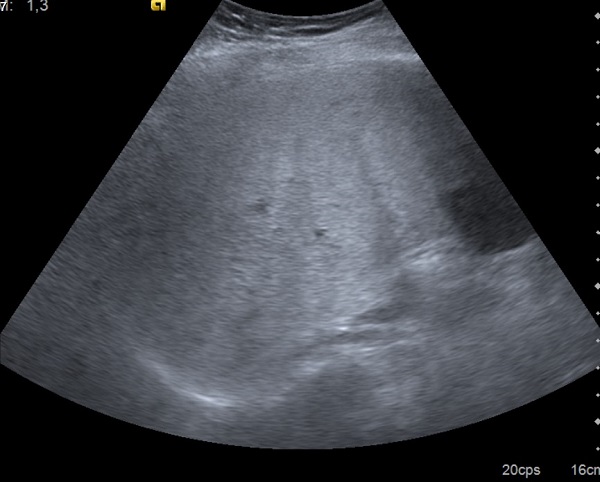

Adolescente varón de 13 años, de origen latinoamericano, controlado en la consulta de Pediatría de Atención Primaria por sobrepeso. Peso: 63,5 kg (P87 1,6 desviaciones estándar [DE]), talla: 155,5 cm (P37 -0,34 DE), índice de masa corporal: 26,26 (P95 1,73 DE), perímetro abdominal 85,5 cm (P98 2,16 DE). Presión arterial de 120/66 mmHg. El resto de la exploración fue normal. No presenta acantosis nigricans. En analítica, ALT 304 UI/l, AST 144 UI/l, GGT 85 UI/l y fosfatasa alcalina 253 UI/l. Colesterol 165 mg/dl. Resto de bioquímica, hemograma y función tiroidea normales. Marcadores de enfermedad celíaca negativos. Se realiza estudio ecográfico en el Centro de Salud visualizando hígado de tamaño normal y contornos regulares, con aumento de ecogenicidad y aspecto esteatósico del parénquima hepático (Fig. 1).

Figura 1. Ecografía abdominal con parénquima hepático con aumento de ecogenicidad